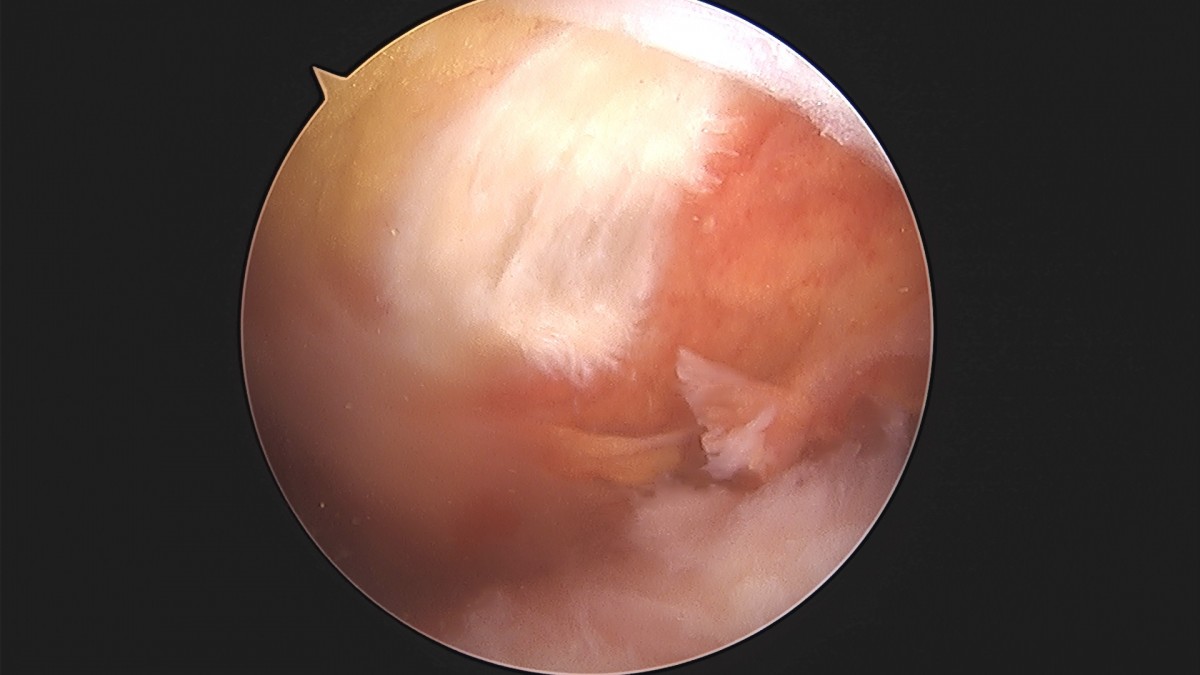

이재상원장님 어깨 견봉하 감압술 및 관절낭 이완술 박창O 환자

dae765e4d9ac96aee867c9d6292d8784_1758004610_4344.jpg